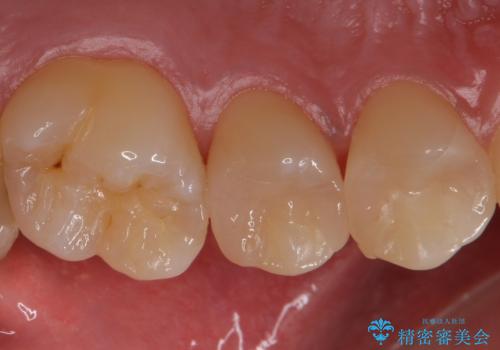

銀歯を目立たなくしたい セラミックインレーでの治療

- 外から見える範囲の銀歯のやり替えをご希望で来院されました。

セラミックインレーでの治療となります。

奥歯とはいえ今回のようなケースでは笑った時に銀歯がちらつきます。

白く目立たないセラミックインレーが入ったことで大変喜んでいただけました。